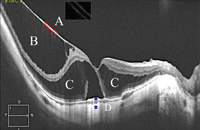

14. Por otra parte, la rigidez de la membrana limitante interna podría deberse a los restos de córtex vítreo adheridos, difícilmente diferenciables por OCT

15,16 (

Figura 4).

Figura 3. A) Perfil tomográfico de un corte vertical cercano a la papila donde se aprecia la tracción centrípeta ocasionada por la rigidez de los vasos retinianos. B) Imagen de fondo de ojo en la que se visualiza la zona de corte del scan B sobre la retina.

Figura 4. Aspecto tomográfico de una típica retinosquisis miópica, en el que se observa cómo la estructura traccional está compuesta por dos capas, probablemente la hialoides posterior aplicada junto con la membrana limitante interna. En el recuadro, aplicando filtros se distinguen ambas estructuras. B) Retinosquisis interna en la que se observan los axones proximales de las células junto al estiramiento de las células de Müller. C) Porción externa de la retinosquisis, en la que se aprecia el estiramiento de las asas de Henle. D) Aspecto típico de la coroides en la región del estafiloma, que se encuentra claramente reducida en grosor en comparación con los ojos emétropes.